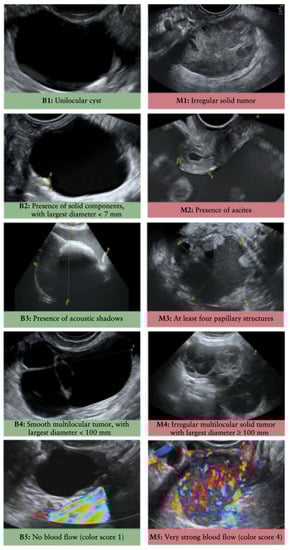

- Kaijser, J.; Bourne, T.; Valentin, L.; Sayasneh, A.; Van Holsbeke, C.; Vergote, I.; Testa, A.C.; Franchi, D.; Van Calster, B.; Timmerman, D. Improving strategies for diagnosing ovarian cancer: A summary of the International Ovarian Tumor Analysis (IOTA) studies. Ultrasound Obstet. Gynecol. 2013, 41, 9–20. [Google Scholar] [CrossRef] [PubMed]